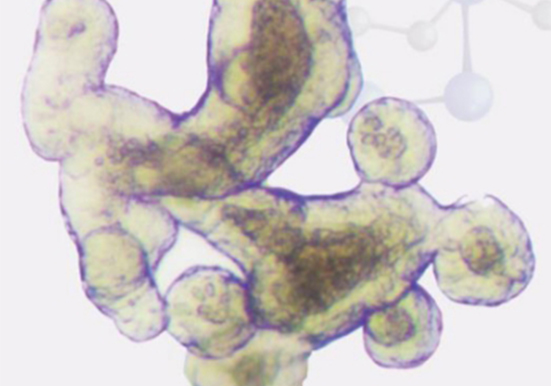

类器官技术服务

类器官技术一站式解决方案1.类器官基因编辑服务:CRISPR/Cas9 基因编辑服务、shRNA 基因编辑服务、项目经验丰富稳定2.类器官技术平台搭建服务:类器官药敏平台、类器官精准···